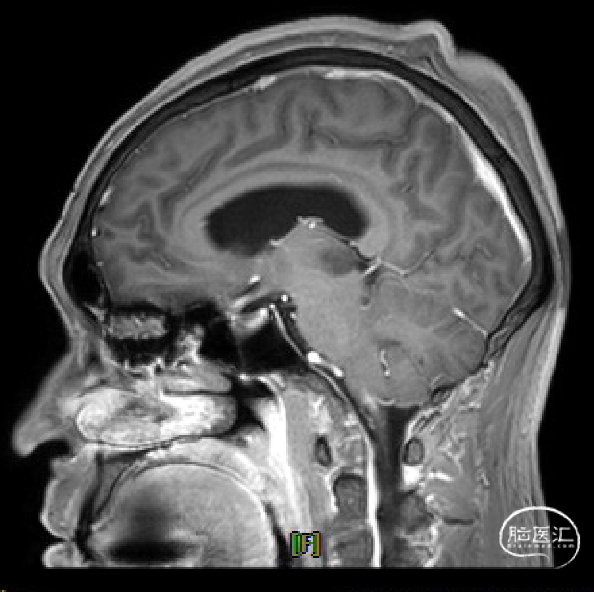

患者5年前无明显诱因出现阵发性头晕,无明显头痛、恶心呕吐等不适,开始未予重视,2022-7-19出现头晕加重,伴视力下降,遂于2022-7-24在当地医院行颅脑MRI提示:松果体区肿瘤伴梗阻性脑积水。

于该院在2022-7-27全麻下行松果体区病灶部分切除活检+神经内镜下第三脑室底造瘘术,术后由于取出肿瘤组织少,未能明确病理结果。患者术后恢复顺利,为进一步治疗就诊于我院。

手术方式

枕下后正中开颅经幕下小脑上入路松果体区肿瘤切除术。